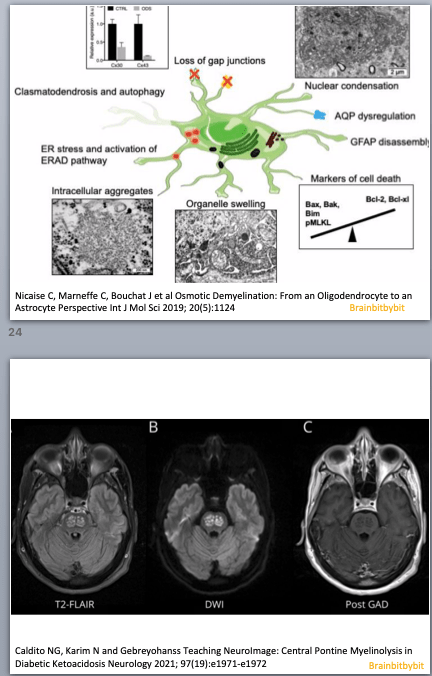

In the hindbrain or rhombencephalon, consisting of pons and medulla oblongata, vital functions are interdispersed with cranial nerve nuclei and ascending and descending tracts. Because of intermixed gray and white matter the pons is especially vulnerable to osmotic demyelination (45). The diverse neurological and psychiatric symptoms observed in patients with pontine osmotic demyelination reflect the different and divergent functions of this region. The brain’s main noradrenaline synthesis site is located in the dorsal pons, the locus coeruleus. From the rostral to the caudal hindbrain, raphe nuclei along the midline contain the majority of serotonergic neurons. The medulla oblongata or bulbus, houses the cardiovascular and respiratory center.